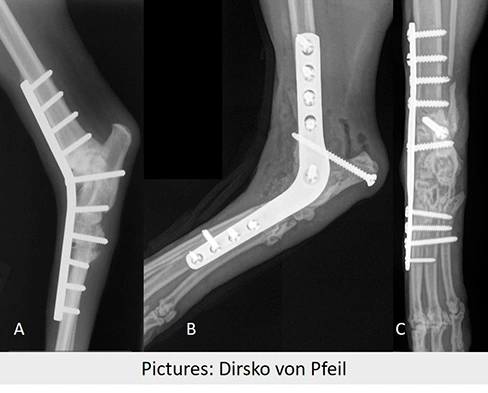

Gelenksversteifung des Tarsalgelenkes (Sprunggelenk). Hund (A), Katze (B,C)